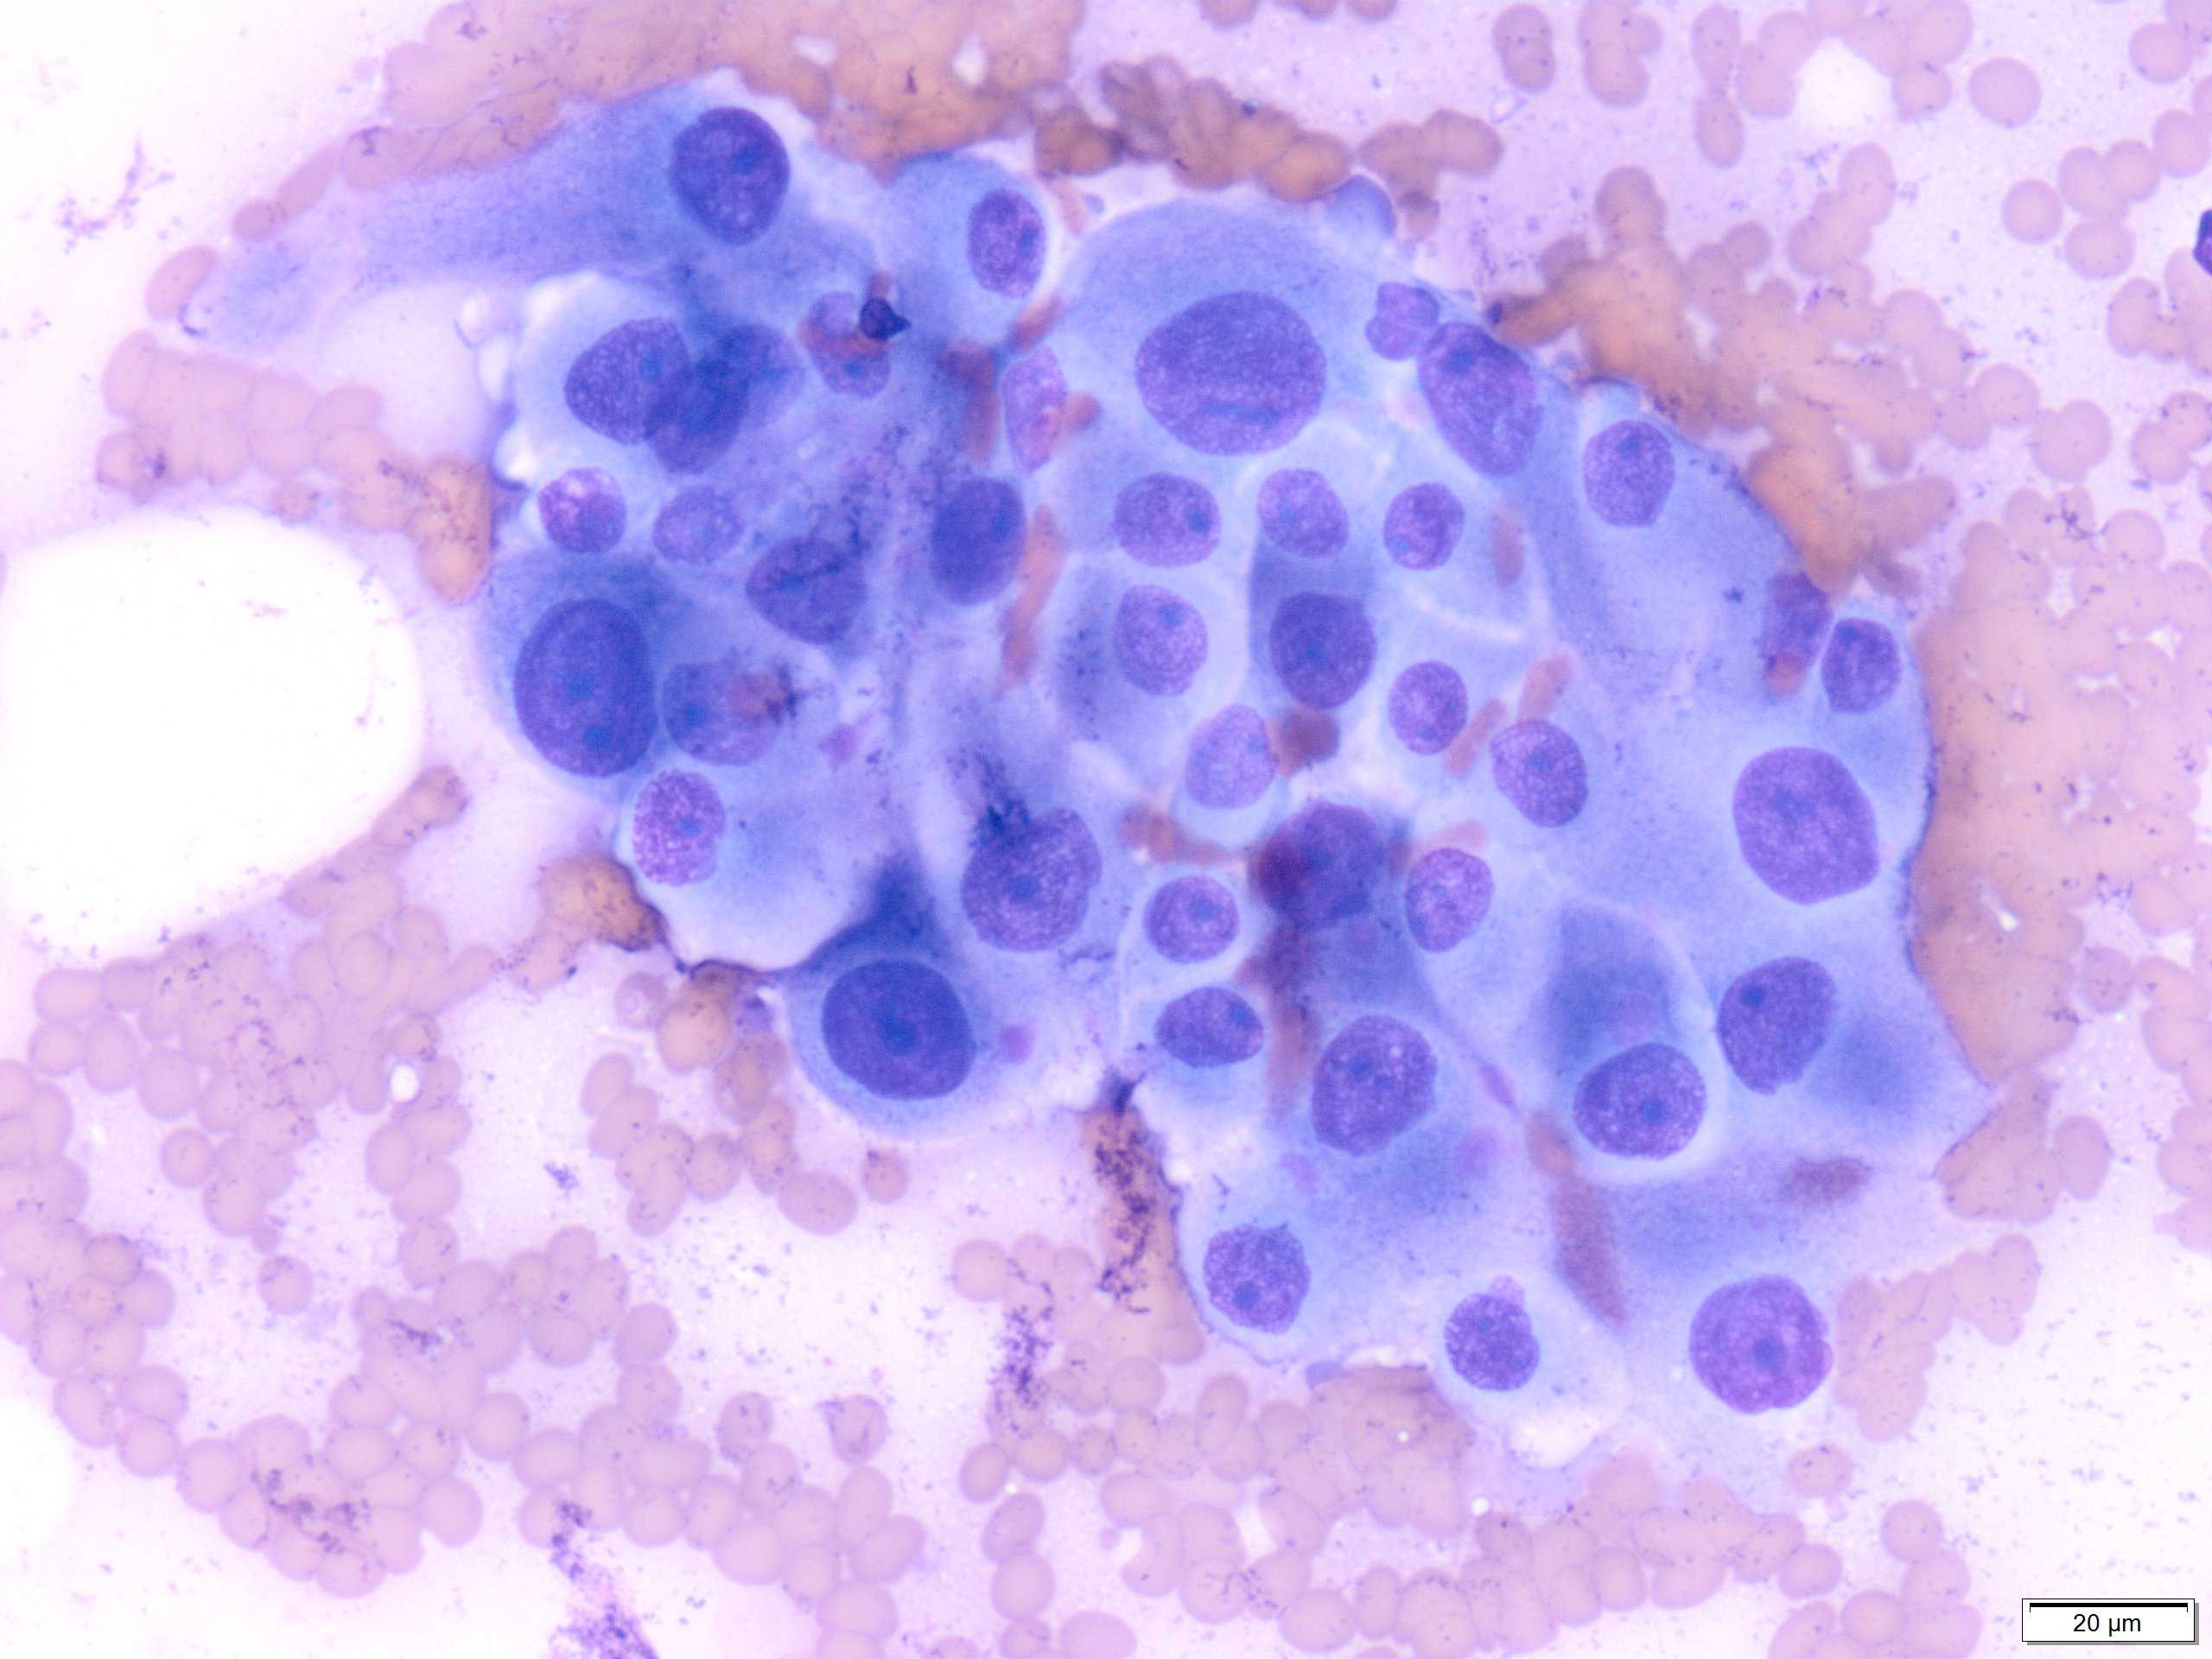

PTC is the most common thyroid malignancy in the United States. It can happen at any age with a female to male ratio of 3:1. The smear are usually cellular with sheets of follicular cells exhibiting nuclear overlapping and/or molding. The cytoplasm can be scant or abundant [squamoid, oncocytic (Picture #2) or vacuolated]. Intranuclear pseudoinclusions (black arrow) are specific to PTC and represent cytoplasmic invaginations. Other non-specific nuclear features include grooves (blue arrow) and nucleoli. Another highly specific feature is the presence of papillae with fibrovascular cores (Picture #3).